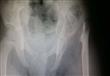

وأوضح الدكتور طارق محروس أبوحليمة - أخصائي العظام وعضو الفريق الطبي الذي أجرى الجراحة للطفلة  لـ"مصراوى" أن الجراحة عبارة عن نقل رأس عظمة الشظية الممدودة، بالشرايين والأوردة، وتشمل مركز النمو العلوى للعظمة، لإعادة بناء مفصل الحوض للطفلة.

وكشف عن الحالة المرضية للطفلة بتعرضها لالتهاب ميكروبى، ما أدى إلى تآكل رأس عظمة الفخذ، ومركز النمو العلوي للعظمة، وخراج بمفصل الحوض للطفلة، وأدخلت وحدة العناية المركزة، لمدة أسبوعين، حتى جرى لها عملية لتصريف الصديد من المفصل وتنظيفه، وبالمتابعة تبين أنها تعانى من استحالة السير والحركة.

وأشار لـ "مصراوي" إلى أن الطفلة أجرت عدة عمليات لمحاولة تعويض رأس عظمة الفخذ، وباءت جميعها بالفشل، وبعد عرضها على الدكتور محمد مصطفى قطب المشرف على فريق وحدة الجراحات الميكروسكوبية التكميلية بالمستشفى وبعد استكمال الفحوصات، قرر إجراء الجراحة.

وقال إن الجراحة استغرق اجرائها 10 ساعات متواصلة، وهي جراحة نادرة من نوعها نظراً لحدوث تآكل فى سطح المفصل والذي يعوضه المفصل الصناعي، حيث من الصعب اللجوء لإجرائها في سن مبكرة، وكذا تعويض مركز النمو الأعلى لعظمة الفخذ، والمسئول عن نمو الطرف السفلى بنسبة حوالي 30%.